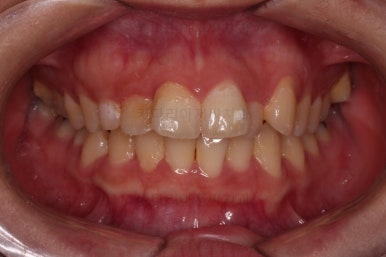

장치 부착 직후의 모습인데요.

보이는 느낌과 장치 때문에 약간 더 튀어나오는 입매 참고 바랍니다.

장치 때문에 입이 나오는 정도는 사람마다 매우 다르므로 실제로 부착해 봐야 아는 경우가 많긴 합니다.

전후 비교입니다.

입매도 약간 나와있던 윗입술이 들어가면서 턱끝의 위치나 느낌도 같이 바뀌었고요.

웃을 때 보이는 치아의 가지런한 느낌과 뻗친 정도는 매우 좋아졌습니다.